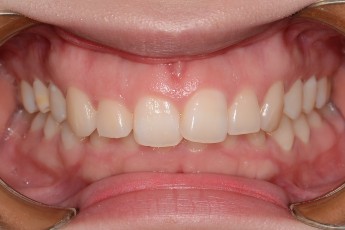

Before

After